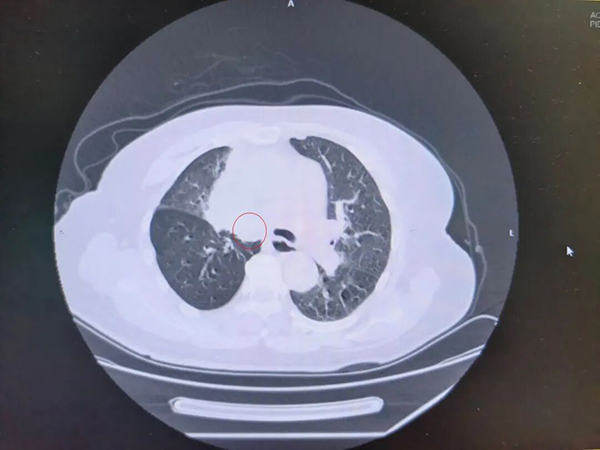

复查CT显示李阿姨肺部肿瘤进展、气道被堵,情况危急。肿瘤科主任茅力平立即组织呼吸与危重症医学科、介入科开展MDT多学科会诊。